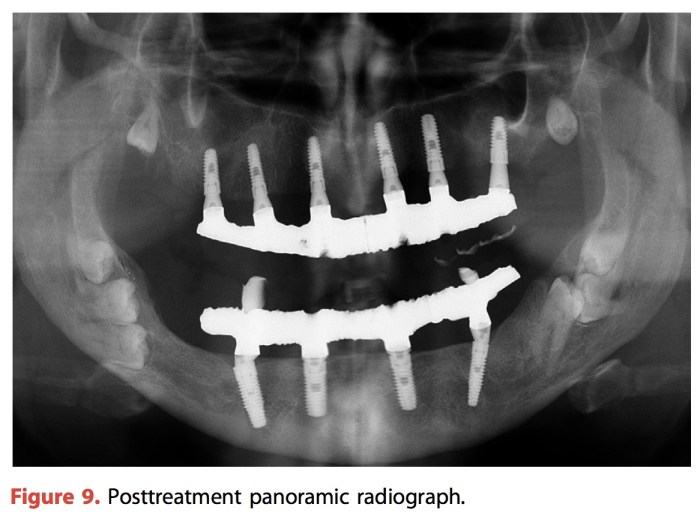

這篇是我對於下顎全口假牙的起始點。不管其他流派如何,我對於下顎全口假牙,最重視的部分叫做“舌頭”。只要患者在張口的時候,舌頭可以保持在向前並且rest在前牙區,而不是retruded position,那就有機會會穩定。另外兩項要注意的分別是:ridge和周圍的組織是否健康?lingual space的有無?因為很難達到這三項的完美,所以我對於下顎的全口假牙基本上會建議,經濟上健康上是健康的,多鎖兩隻標準size的植體會好用很多。